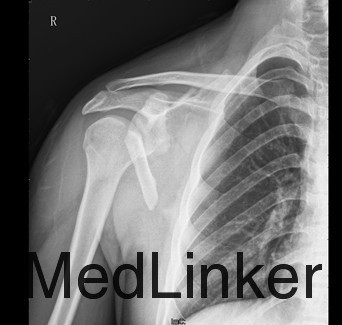

患者男,18岁,因“车祸伤致右肩部疼痛伴活动受限15天”入院。患者入院前15天乘坐摩托车时不慎发生车祸,伤及右侧肩部。伤后即往当地医院,诊断为右肩胛骨粉碎性骨折,行输液及对症治疗(具体不详),右绷带包扎固定,患者患者为求进一步治疗于今日来我院,门诊以右肩胛骨粉碎性骨折收入我科。

查体:右侧肩背部稍肿胀,局部皮肤无破溃。右肩背部触痛明显,右肘、右前臂、手部无明显触痛,无感觉减退,右桡动脉尺动脉搏动可扪及。右侧肩关节因疼痛拒动,右肘、右腕关节,手指活动无受限。左上肢及双下肢肌力正常、活动无受限。 辅查:X片、CT示右侧肩胛骨皮质连续性中段,骨折块移位,提示右肩粉碎性骨折。

诊断:右肩胛骨粉碎性骨折 治疗:拟行右肩胛骨骨折切开复位内固定术